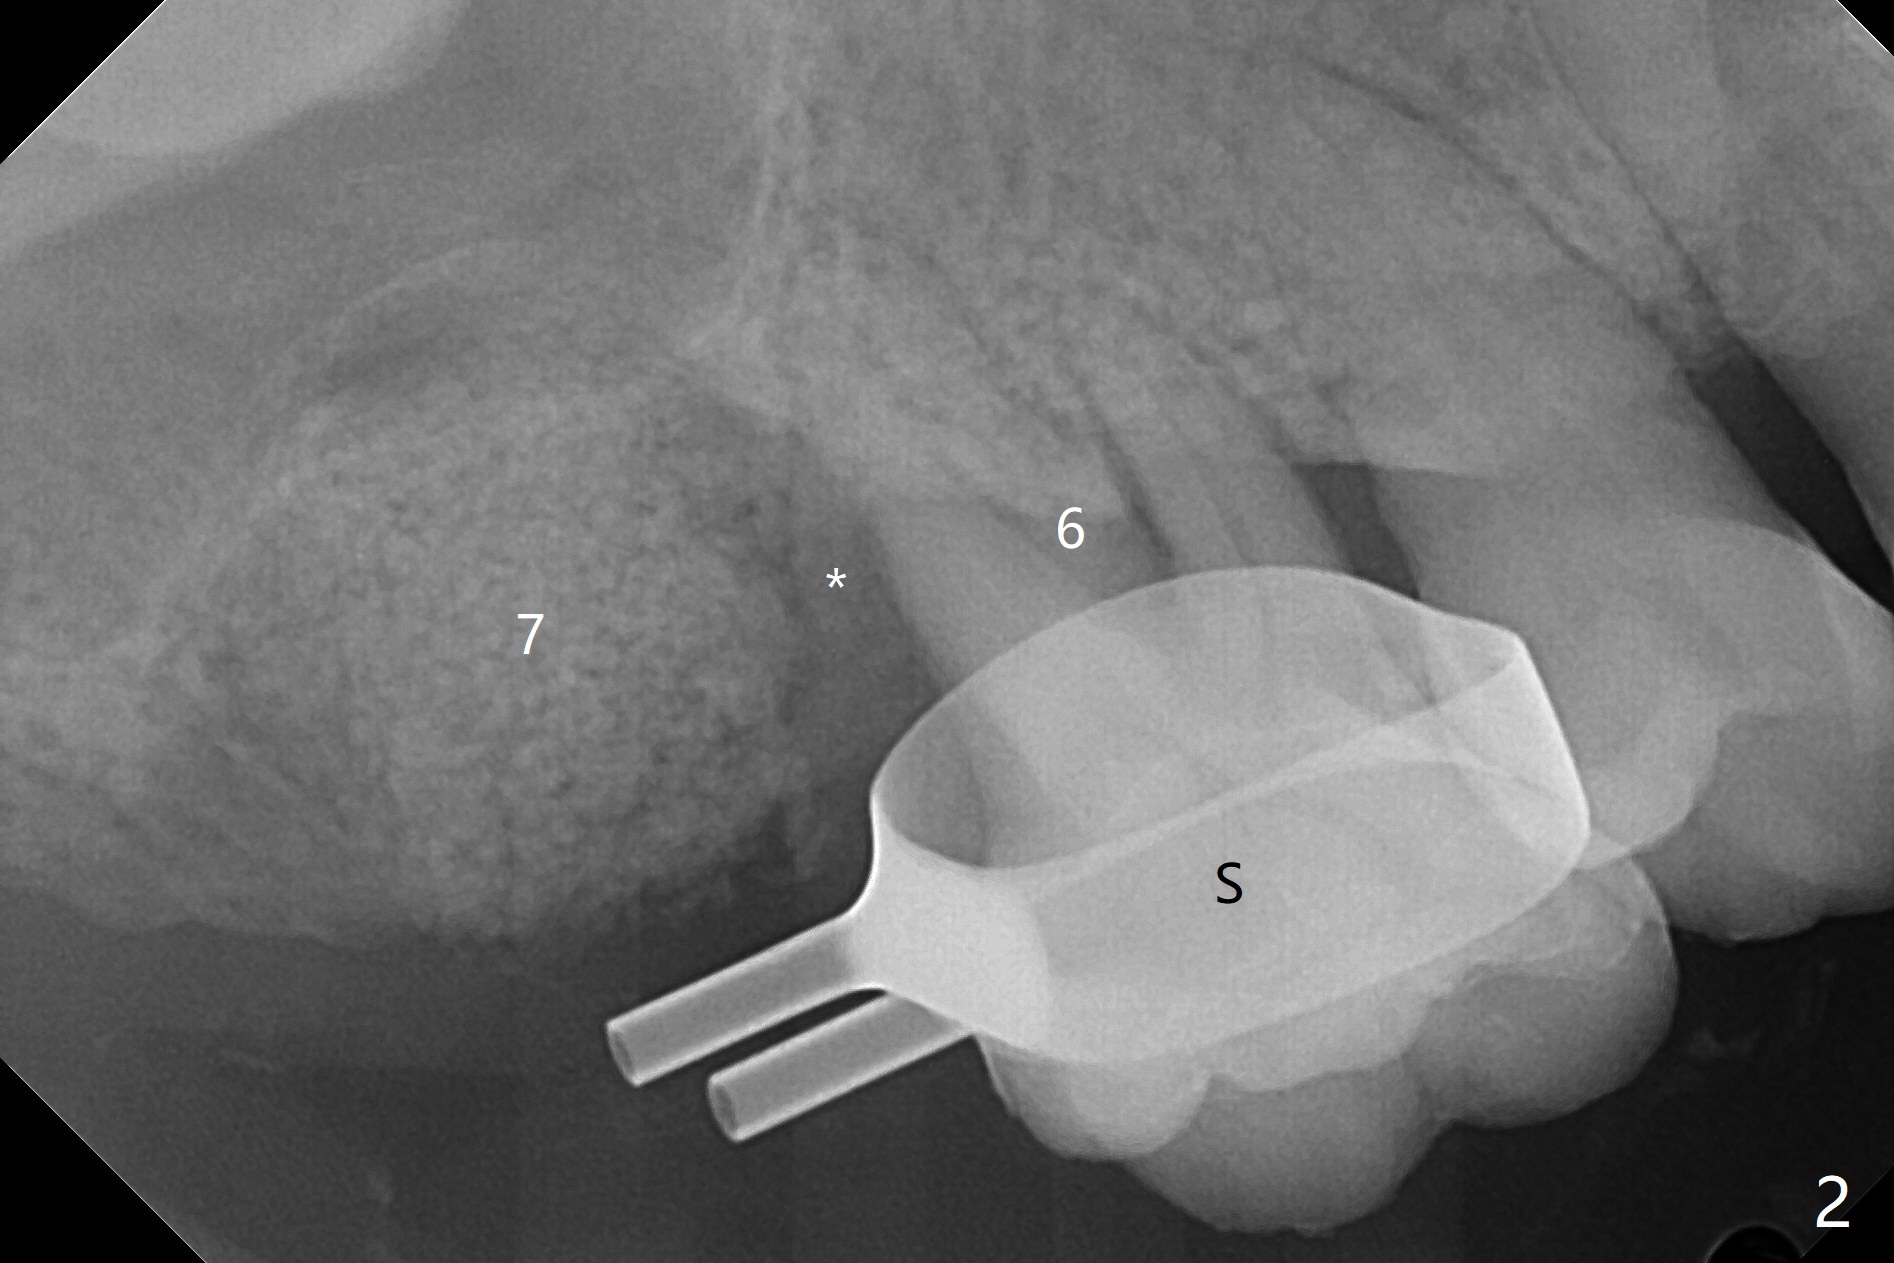

尽管右上第一,二磨牙骨质吸收严重,为了保持牙乳头,先拔除有症状第二磨牙,但是后者牙槽窝与第一磨牙之间好像没有软组织(图二:*),所以骨粉(图一,二:7)无法从前者推入后者(图二(下一个成功病例))。骨粉表面放置6个月吸收膜(GEM Cap(图三::C)),使用牙周胶水固定,而且装置牙齿空间维持器(图二:S)和牙周敷料强化固位。牙齿拔除证实腭侧牙槽窝(图四:P)上颌窦底板穿孔(^;但是没有漏气)。虽然病人已经服用Amoxicillin一周以及Z Pack(两颗,术前),为了防止感染介入上颌窦,穿孔冠部放置胶原塞(图五:黄色),然后放置骨粉(红色)。后者仿佛增加骨质高度不少(图二)。如果不够,以后再做提升。多亏间隙保持器,牙周敷料术后4天没有松动迹象(图六)。术后三周敷料颊侧有些破裂(图七),而舌侧完整(图八)。嘱咐病人正常刷牙和水牙线,让敷料自行脱落。其实术后六周敷料仍在原位,不可吸收膜粘附于敷料,两者一起去除,伤口愈合(图九),骨粉好像没有损失(图十)骨高度减少。术后4个月骨质高度继续减少(图十一)。植骨后骨质高度还与邻牙一致,密度低,可植入5x7.3毫米植体(图十二)。